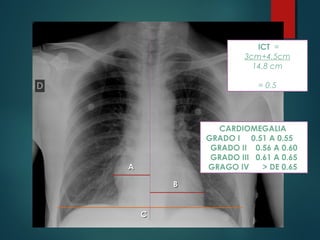

Índice Cardiotorácico:

1. Trazar la línea media

2. Medir la distancia entre el

punto más distal de cada

borde cardiaco y sumarlas

3. Medir el diámetro transverso

de la caja torácica

1. Sumar las distacias y

dividirlo entre el diámetro

transverso y multiplicarlo

por 100

ICT = A+B

C

Normal: <0.5

AA

BB

CC

ICT =

3cm+4.5cm

14.8 cm

= 0.5

CARDIOMEGALIA

GRADO I 0.51 A 0.55

GRADO II 0.56 A 0.60

GRADO III 0.61 A 0.65

GRAGO IV > DE 0.65

RADIOGRAFÍA DE TORAX ÍndiceCardiotorácico: 1. Trazar la línea media 2. Medir la distancia entre el punto más distal de cada borde cardiaco y sumarlas 3. Medir el diámetro transverso de la caja torácica 1. Sumar las distacias y dividirlo entre el diámetro transverso y multiplicarlo por 100 ICT = A+B C Normal: <0.5

AA BB CC ICT = 3cm+4.5cm 14.8 cm =0.5 CARDIOMEGALIA GRADO I 0.51 A 0.55 GRADO II 0.56 A 0.60 GRADO III 0.61 A 0.65 GRAGO IV > DE 0.65